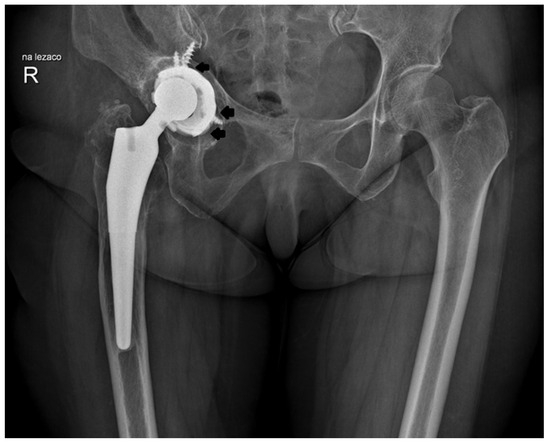

High Risk of Revision Associated with the L-Cup Titanium Alloy Porous Coated Acetabular Component in Primary Total Hip Arthroplasty: Minimum Follow-Up of 14 Years

by Marek Drobniewski, Kacper Ruzik, Bartosz Gonera, Łukasz Olewnik, Adam Borowski, George Triantafyllou and Andrzej Borowski

J. Clin. Med. 2025, 14(4), 1301; https://doi.org/10.3390/jcm14041301 - 15 Feb 2025

Cited by 2 | Viewed by 1584

Background: Hip joint pain due to arthritis is a prevalent issue in adults, often necessitating surgical intervention such as total hip arthroplasty (THA). This procedure has been celebrated for its reliability; however, successful outcomes depend on numerous factors. Current advancements are focused on [...] Read more.

Background: Hip joint pain due to arthritis is a prevalent issue in adults, often necessitating surgical intervention such as total hip arthroplasty (THA). This procedure has been celebrated for its reliability; however, successful outcomes depend on numerous factors. Current advancements are focused on improving implant design and surgical methodologies. This study aimed to evaluate the long-term clinical and functional outcomes of uncemented total hip arthroplasty utilizing the L-Cup acetabular component. Methods: Between February 1999 and November 2010, 351 L-Cup components were implanted in 315 patients. A follow-up period ranged from 14 to 25 years. The clinical outcomes were assessed using the modified Merle d’Aubigné and Postel (MAP) classification and patient satisfaction was measured using a Visual Analog Scale (VAS). Results: Postoperative evaluations showed significant improvement, with VAS scores decreasing from a mean of 7.2 to 2.1, indicating substantial pain alleviation. The modified MAP classification showed a significant improvement of 6.3 points throughout the follow-up period. The results revealed that 49.5% of the cases were classified as excellent, while 20.5% had poor outcomes due to prosthesis loosening. According to the Kaplan–Meier estimator, the 5-year survival rate for the acetabular component was 97.78%, with survival rates of 90.5% at 10 years, 80.45% at 15 years, and 73.79% at 20 years. Conclusions: Total hip arthroplasty is an effective treatment for advanced degenerative joint diseases. While significant postoperative improvements were documented, the observed prosthesis loosening in 20.5% of cases raises concerns about the long-term effectiveness of the L-Cup acetabular component and suggests the need for further refinement in surgical techniques and implant design. Full article